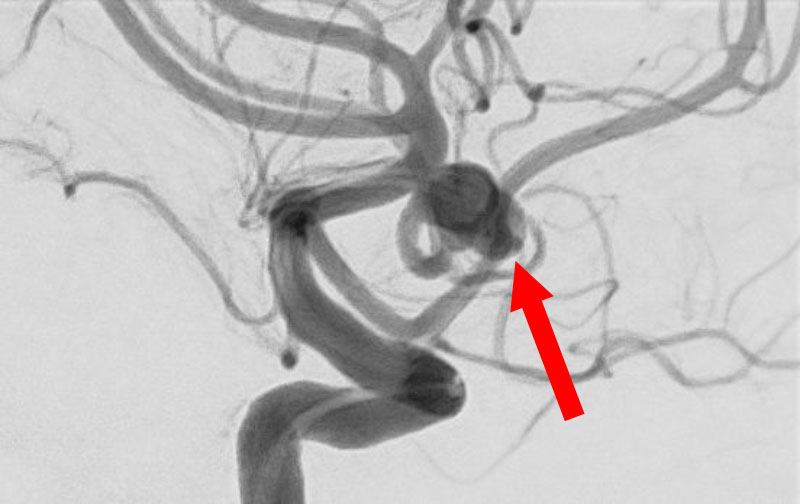

'26年4月

左内頚動脈脳動脈瘤

70代

大阪府の病院

No.1630 手術前

No.1630 手術中

No.1630 手術後